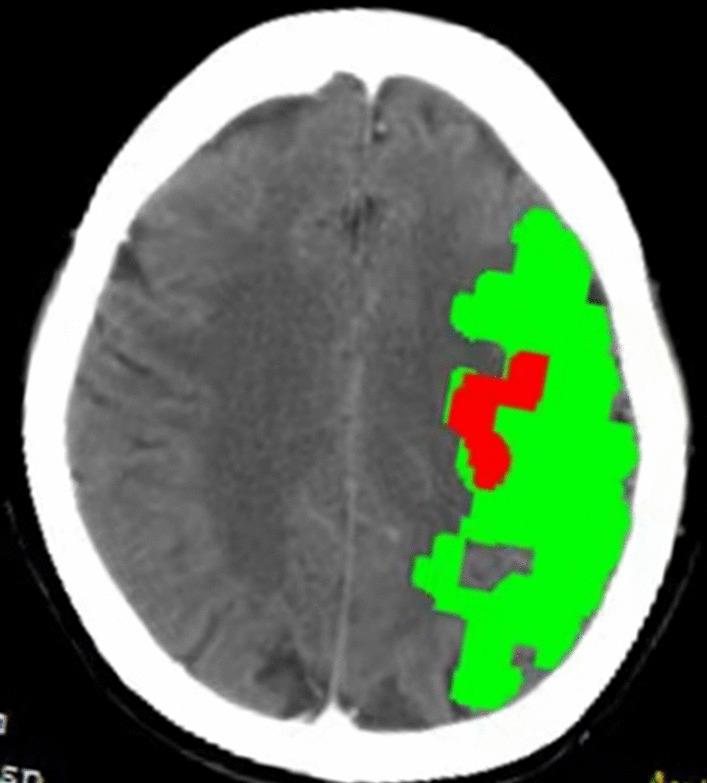

Elevated NT-proBNP levels are associated with CTP ischemic volume and 90-day functional outcomes in acute ischemic stroke: a retrospective cohort study.

To investigate the impact of N-terminal pro-B-type natriuretic peptide (NT-proBNP) on CTP infarct core volume and poor 90-day functional outcomes in acute ischemic stroke (AIS).

NT-proBNP was positively correlated with CTP ischemic volume (p < 0.001), infarct core volume (p < 0.001), and ischemic penumbra volume (p < 0.001). Univariate analysis showed that the influence of NT-proBNP and functional outcomes were statistically significant in model 1 (p = 0.002). This phenomenon was persistent after adjusted for age, sex, and body mass index in model 2 (p = 0.011), adjusted for SBP, current smoking, family history of stroke, hypertension, and diabetes mellitus in model 3 (p < 0.001), and adjusted for TnI, D-dimer, PLT, Cr, TC, TG, HDL-C, treatment decisions, and NIHSS score in model 4 (p = 0.027). A high NT-proBNP was associated with a high 90-days mRS score among the total population, IV rt-PA, and standardized treatment groups, but not in IV rt-PA + EVT, EVT, and EVT/IV rt-PA + EVT groups.

Elevated NT-proBNP levels reveal large CTP infarct core volume and poor 90-day functional outcome in AIS. NT-pro BNP is an independent risk factor for functional outcomes.